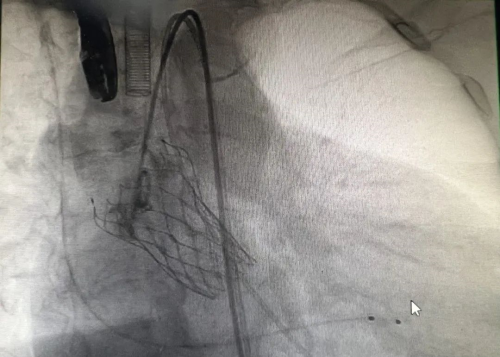

心胸外科副主任、主任医师杨继承接诊后,提出了一个创新的解决方案——TAVR手术。这项技术通过微创的方式,仅需在患者大腿根部的股动脉处开一小口,即可利用导管将人工心脏瓣膜精准送达病变的主动脉瓣位置并完成置换,避免了传统手术的大创伤和高风险。

经过充分的准备,7月30日,手术在导管室内顺利进行。在麻醉医师的精心操作下,超声科医师迅速置入食道超声以监测手术进程。杨继承主任医师带领的心胸外科医师团队凭借高超的技艺,在严爷爷左右股动脉处各开一微小切口,随后在导丝引导下,成功将人工瓣膜送达主动脉瓣位置并完美释放。术后,严爷爷的血流动力学立即得到显著改善,各项生命体征平稳。